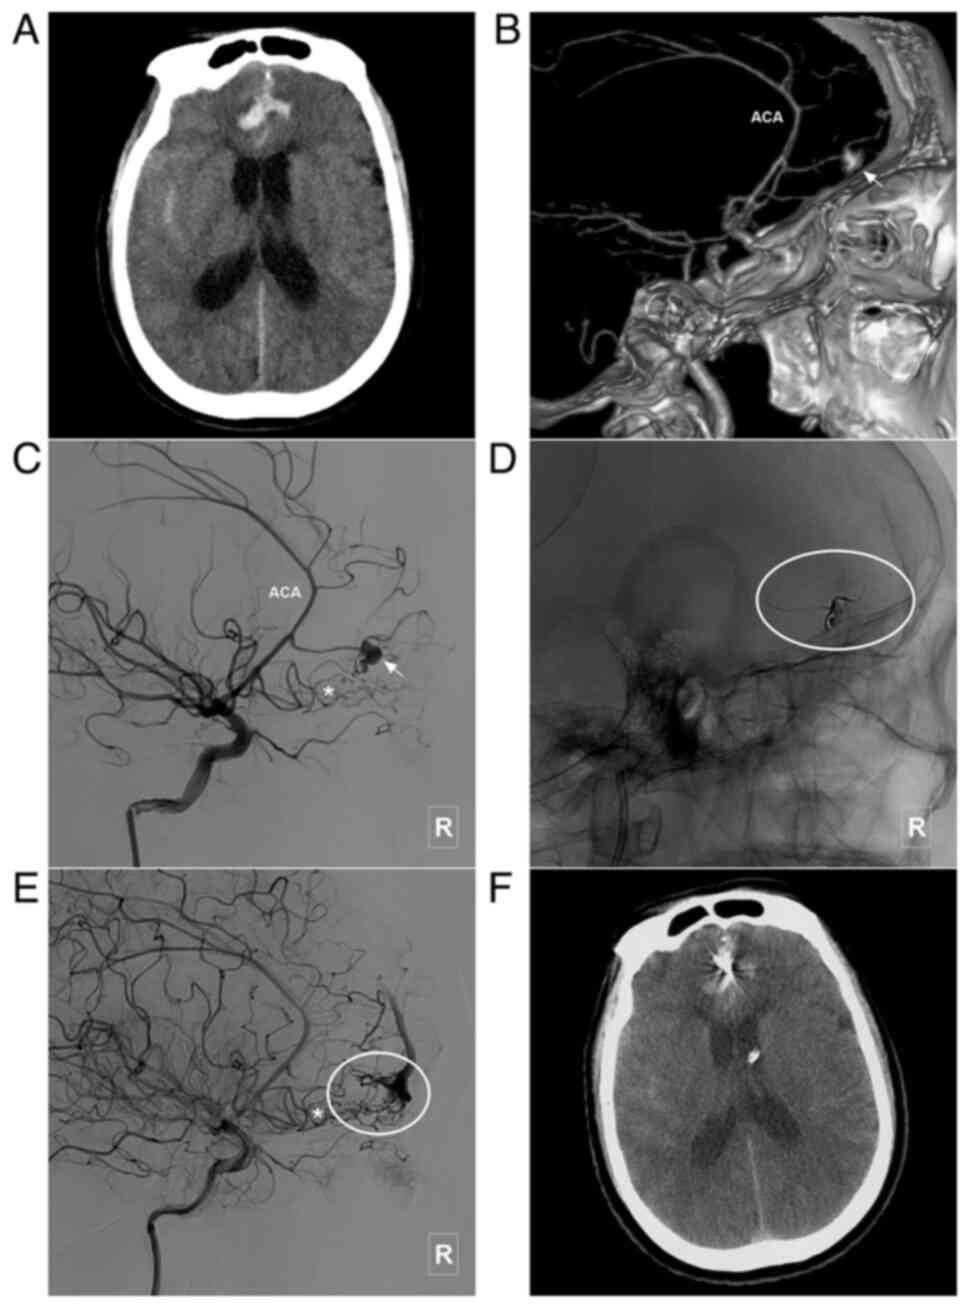

Figure 7

Typical case of a type III BAVM with multiple flow-related aneurysms in the ACA trunk. (A) Head CT scam illustrating a subarachnoid hemorrhage in the interhemispheric fissure. (B) Head CTA illustrating a BAVM (encircled area) supplied the ACA, MCA and PCA, and which drained to the sagittal sinus. The ACA is the main feeding artery, with multiple flow-related aneurysms (arrow and arrow head). (C) Angiogram of the left vertebral artery shows that the posterior circulation is involved in the blood supply of the BAVM. (D) A stent was used to assist in coiling of the aneurysm (arrow) in the ACA. (E) MRI at 3 days post-treatment reveals a new hemorrhage in the interhemispheric fissure, which is considered to be caused by re-rupture of the aneurysm. (F and G) Parent artery occlusion is performed to occlude the aneurysm and the parent artery (arrow). (H) Angiogram of the right internal carotid artery in venous phase illustrating retrograde blood supply from the BAVM to the frontal lobe (encircled area) through the ACA (asterisk). ACA, anterior cerebral artery; BAVM, brain arteriovenous malformation; CT, computed tomography; CTA, computed tomography angiography; L, left; MCA, middle cerebral artery; MRI, magnetic resonance imaging; PCA, posterior cerebral artery; R, right.